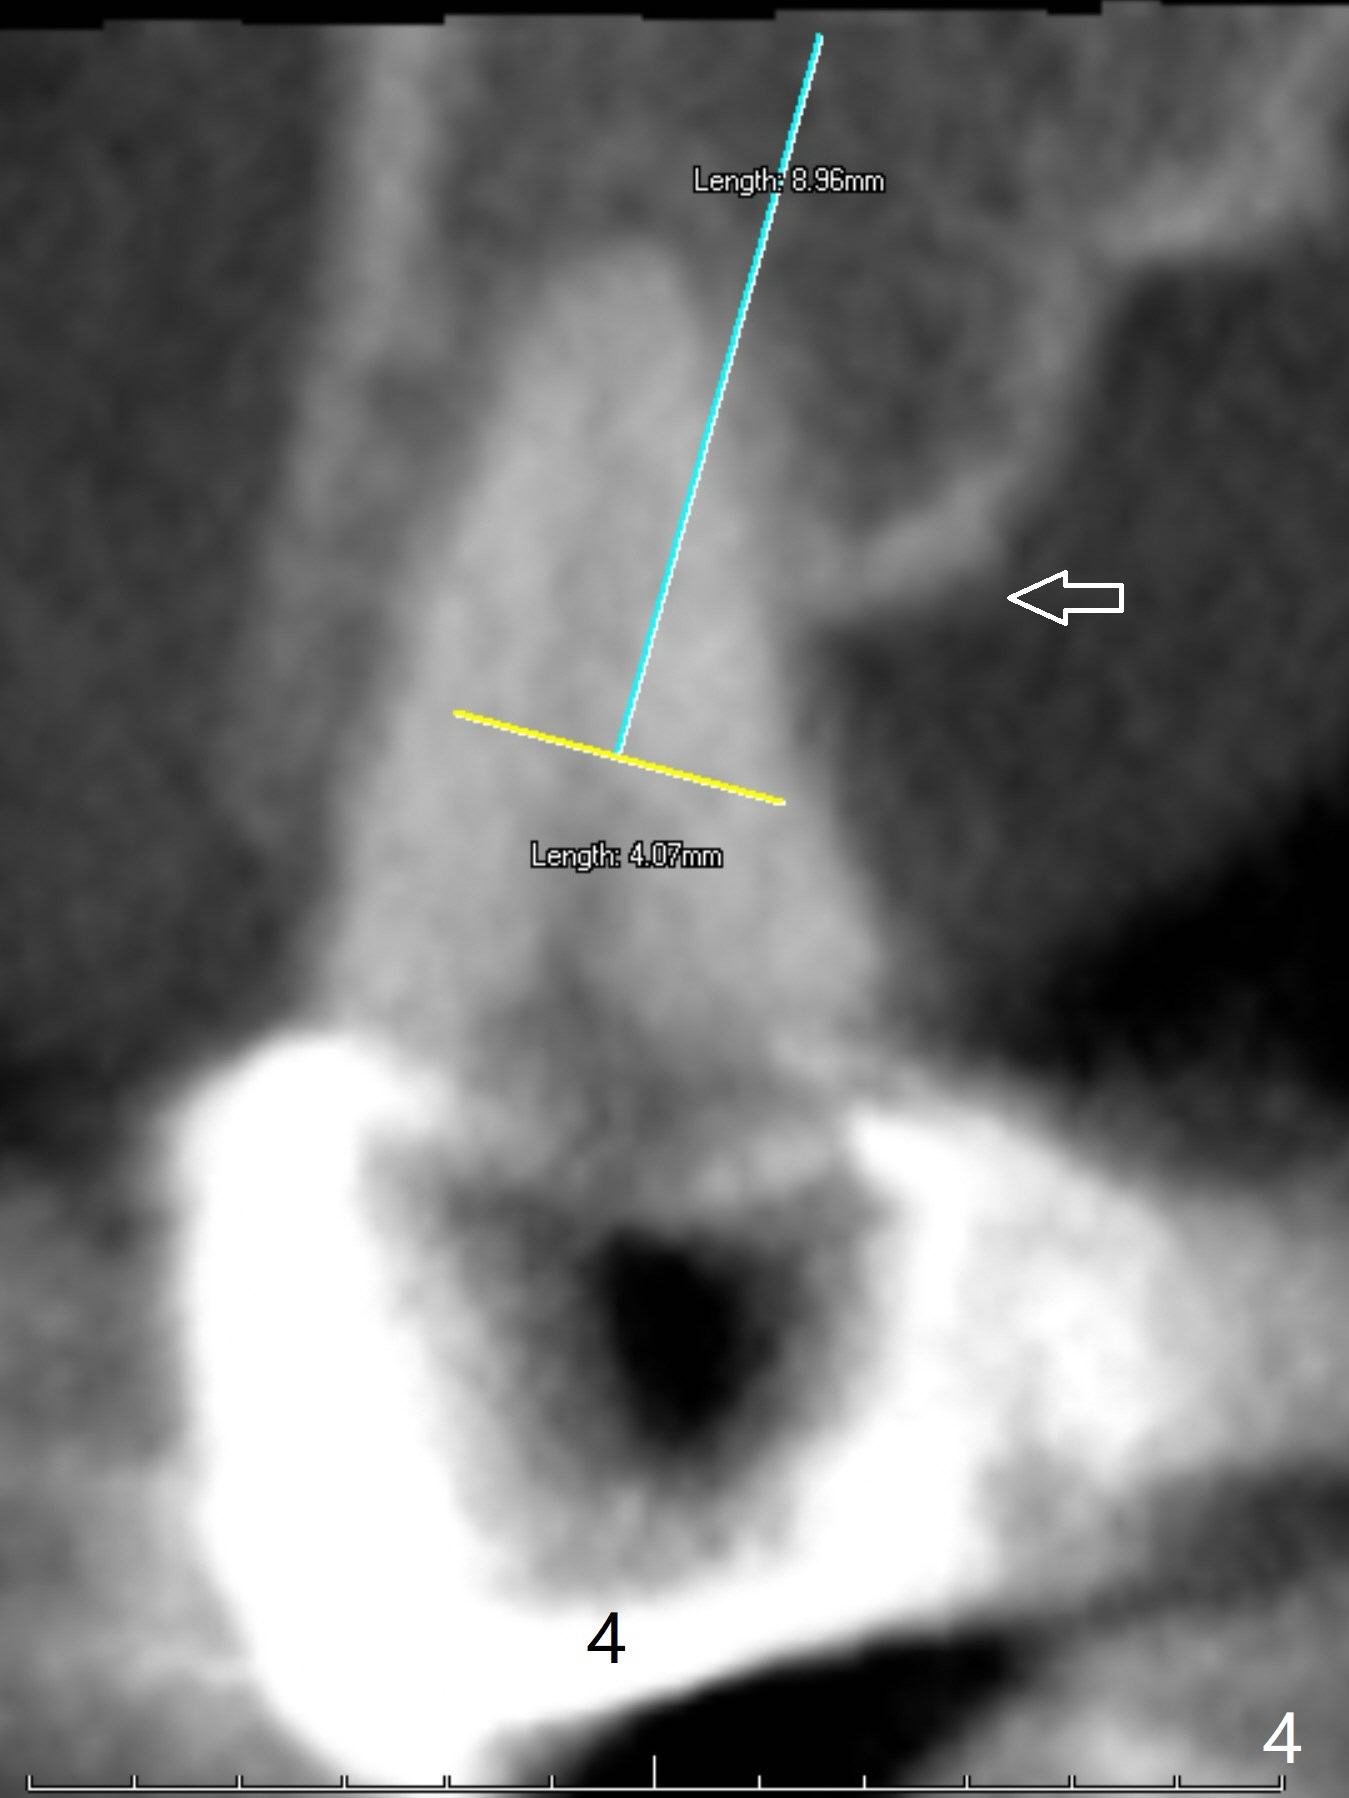

A 43-year-old woman has a failing upper right bridge (Fig.1: #2-5). While the abutment at #5 has apparently palatal open margin (Fig.2,3) and that at #4 has severe palatal bone loss (Fig.4 arrow), that at #2 has the poorest prognosis (Fig.6,7). Panoramic X-ray or PAs will be taken because of CBCT cone cut when the patient returns for #30 and 31 post-implant follow-up. Alginate impression will be taken for the upper right quadrant for provisional. The bridge will be sectioned between #3 and 5 (Fig.1 red lines) to determine salvageability of the abutments at # 4 and 5. If the latter are ok, the abutment at #2 will be extracted (expected to be loose) and implants will be placed at #2 and 3. If #4 is bad while #5 is ok, the former will be extracted and implants will be placed at #2 and 4 with a bridge. If #5 is bad while #4 is ok, implants will be placed at #2, 3 and 5.